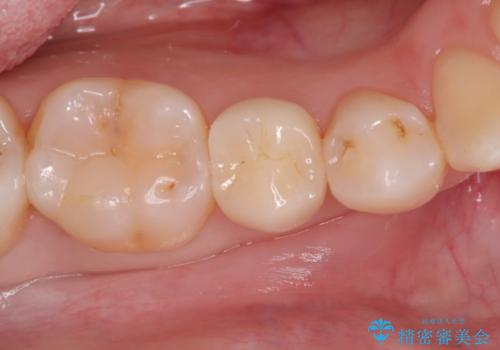

- 金属の詰め物を外して、セラミックインレーを入れたいと来院された患者様です。

奥歯に虫歯も認め、3歯の治療を来院回数2回で終了で終了しています。

当院でのセラミックインレーはすべてe-maxと呼ばれる高強度セラミックにて製作されます。

また、製作方法もプレスと呼ばれる方法を用いることで精度を高めています。